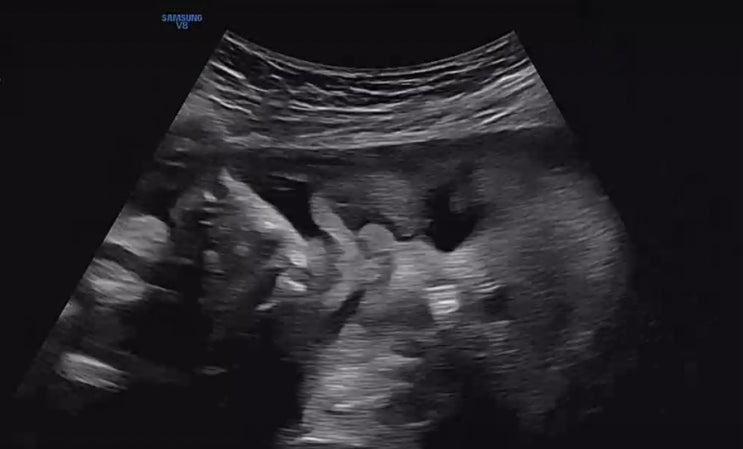

37주 0일 출산-도치맘이 되다

너무 귀엽고 예쁜 울아가를 드디어 낳았다. 조산이슈-양수부족으로 겨우 37주 0일에 낳았지만 2.75kg으로 ...

36주 눕눕일기-마지막 임신일기, 양수부족, 제왕절개

36주가 되니 희한하게 수축이 수그러 든 느낌이었다 태동도 엄청 좋아서 이러다가 만출하겠다는 생각을 했...